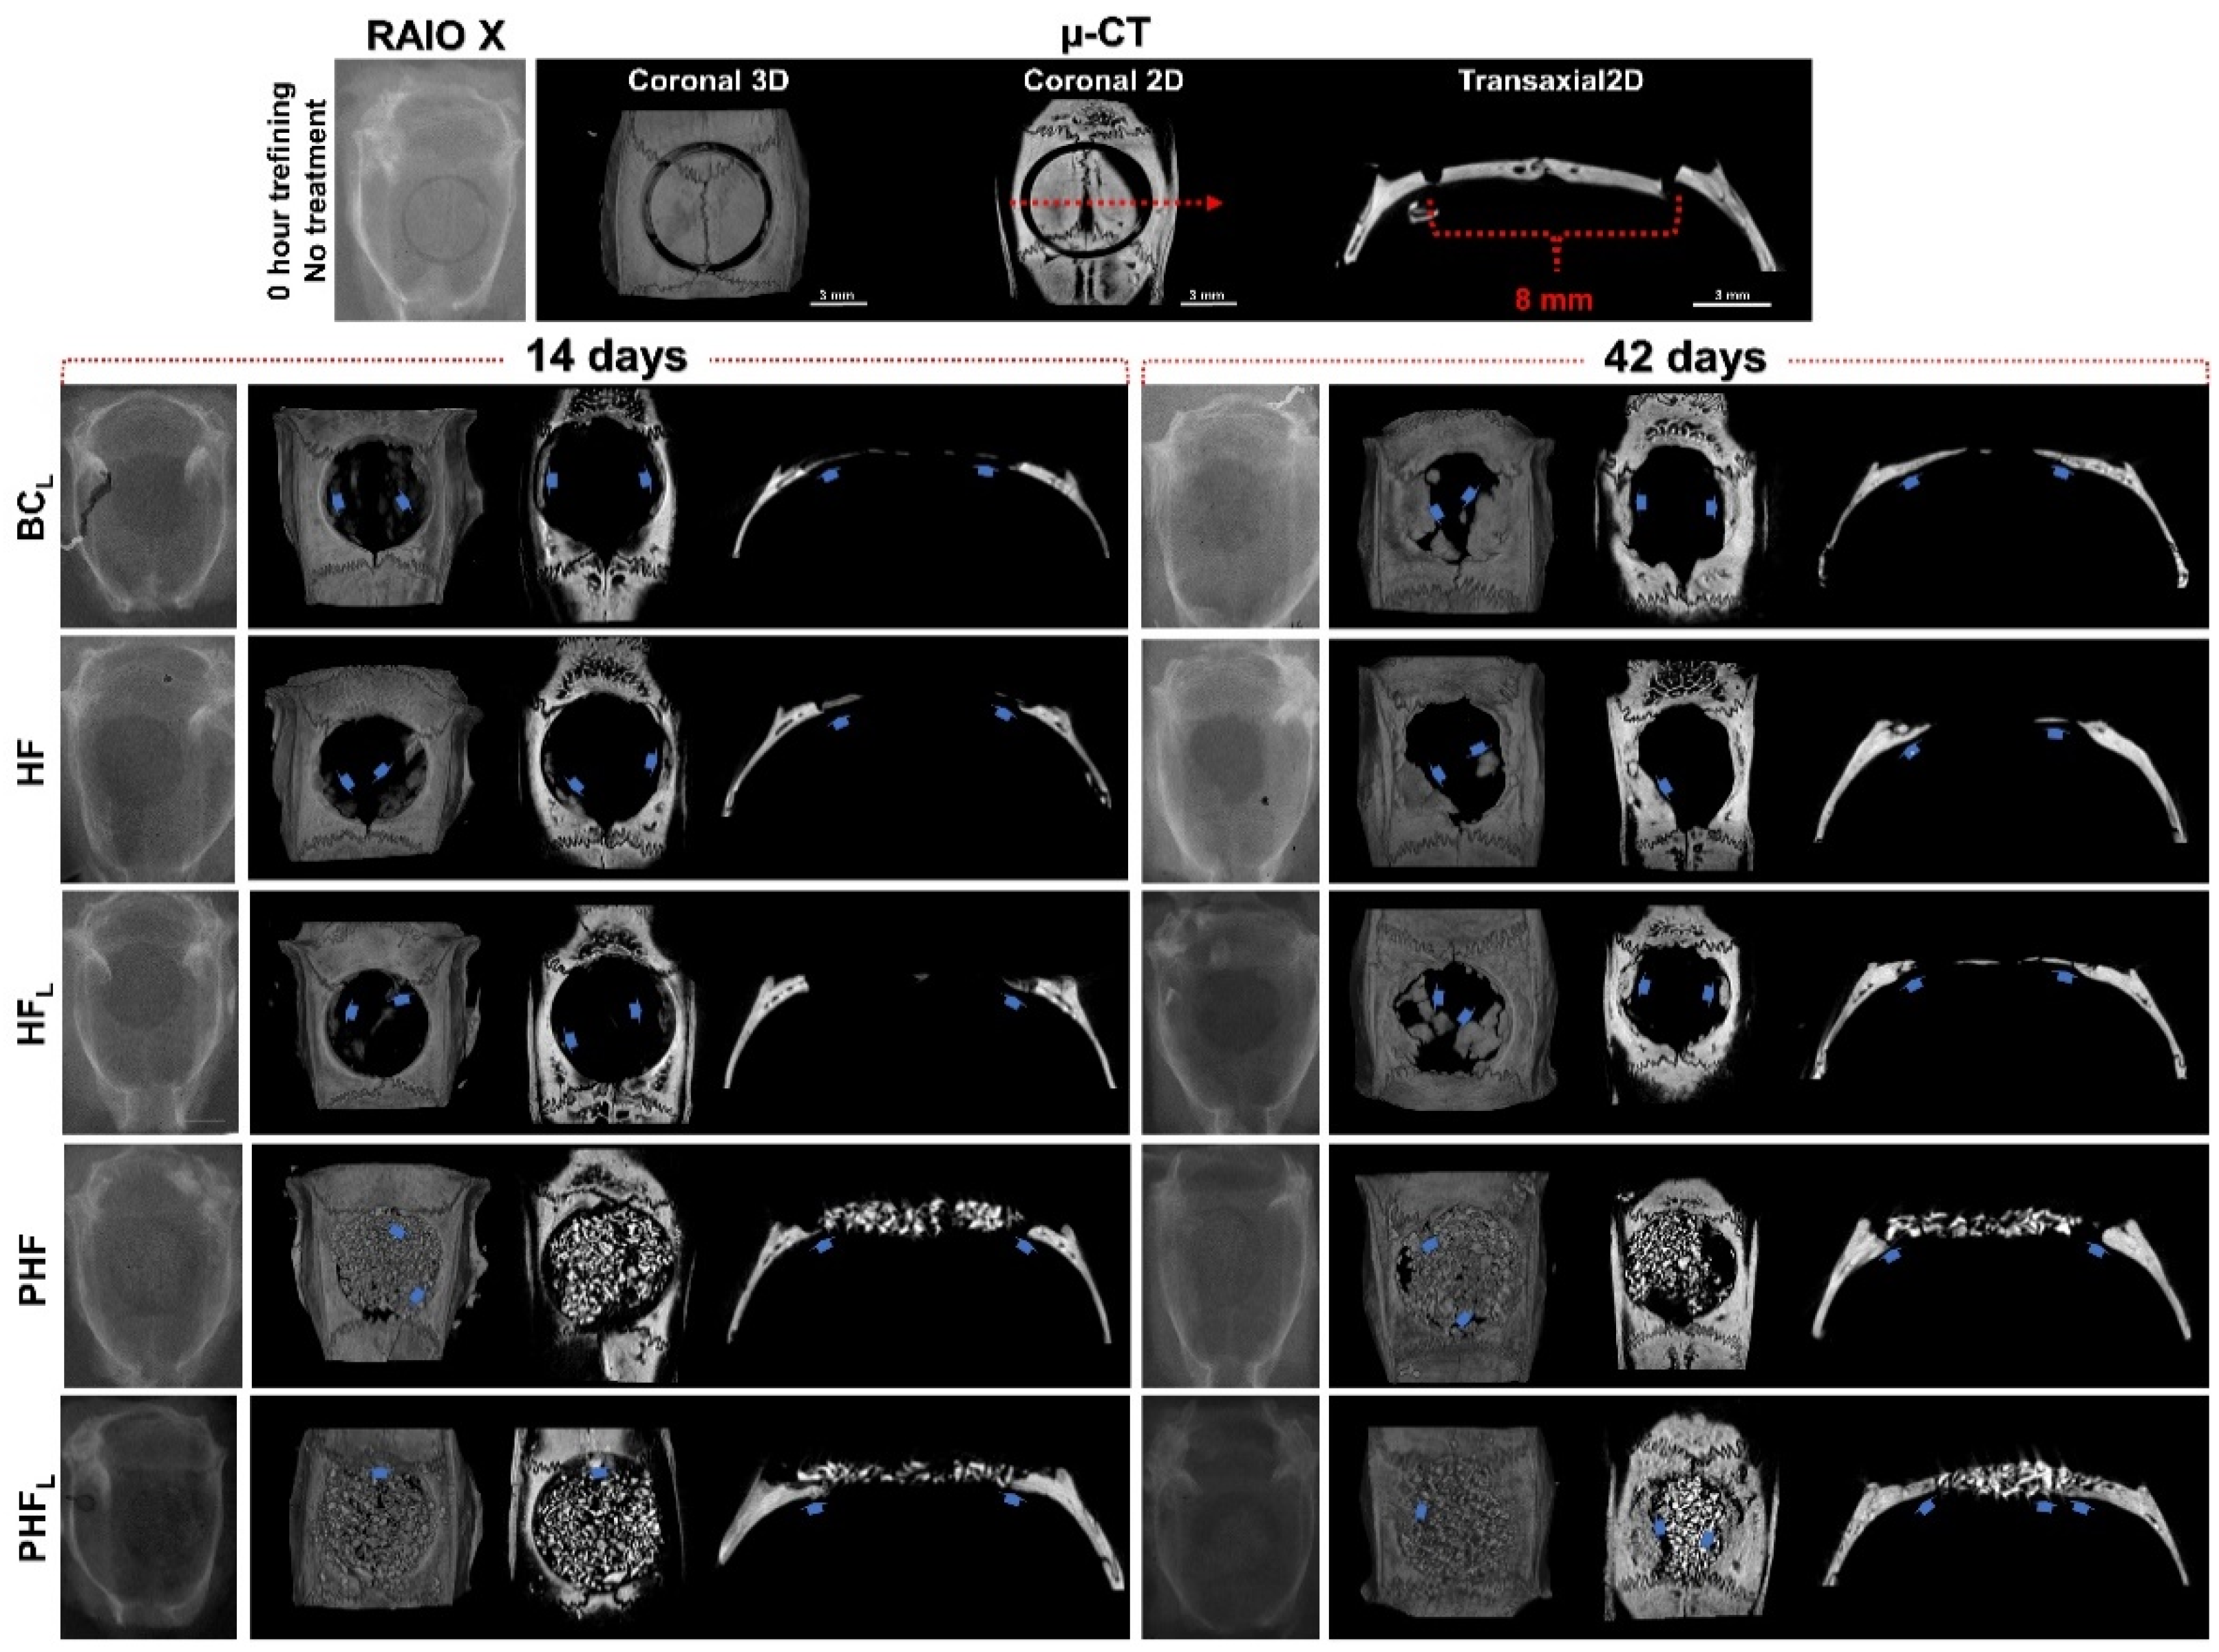

2.1. X-ray Computed Microtomography (µ-CT)

4.7. X-ray Computed Microtomography (µ-CT)